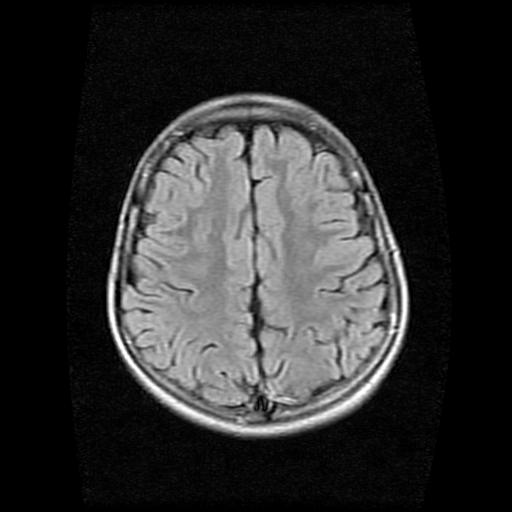

9岁女孩,三岁时诊断为癫痫,一直服丙戊酸钠,现患者一般情况良好,家长复查核磁片,看能否停药..

巨脑回